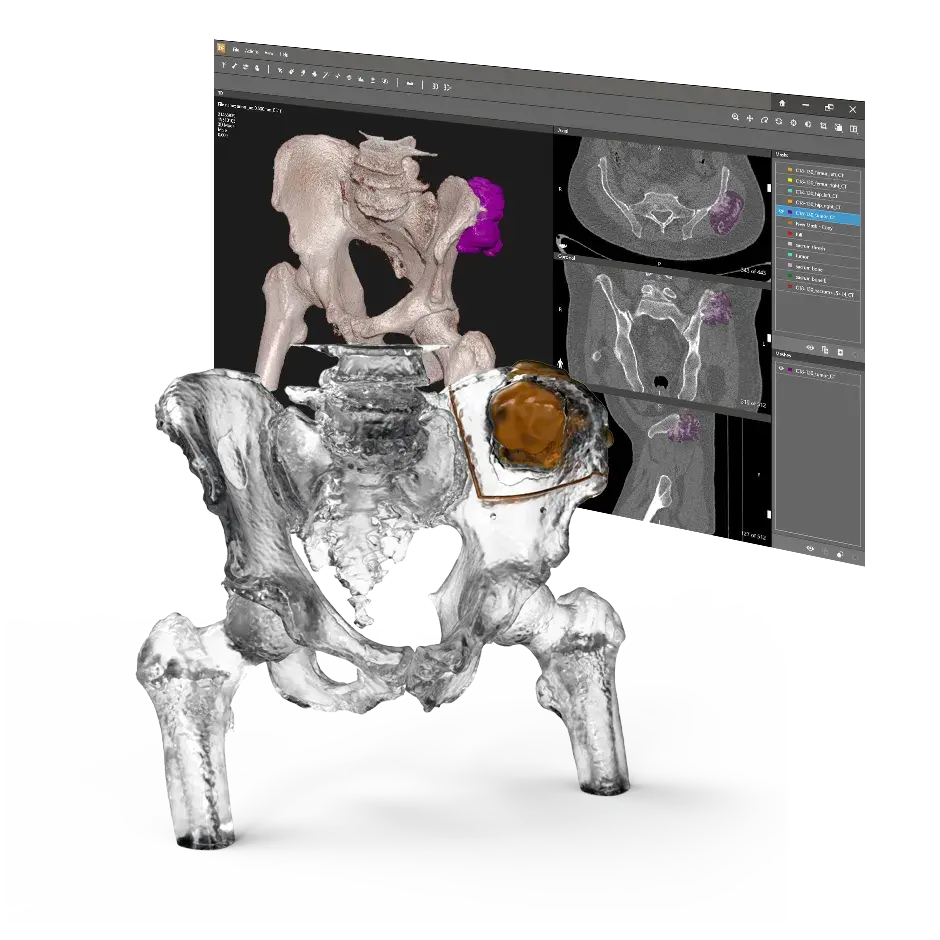

Advanced Software

Full-color anatomic models to aid in visualization of complex structures

DICOM에서 PRINT로

DICOM 3D 모델 소프트웨어